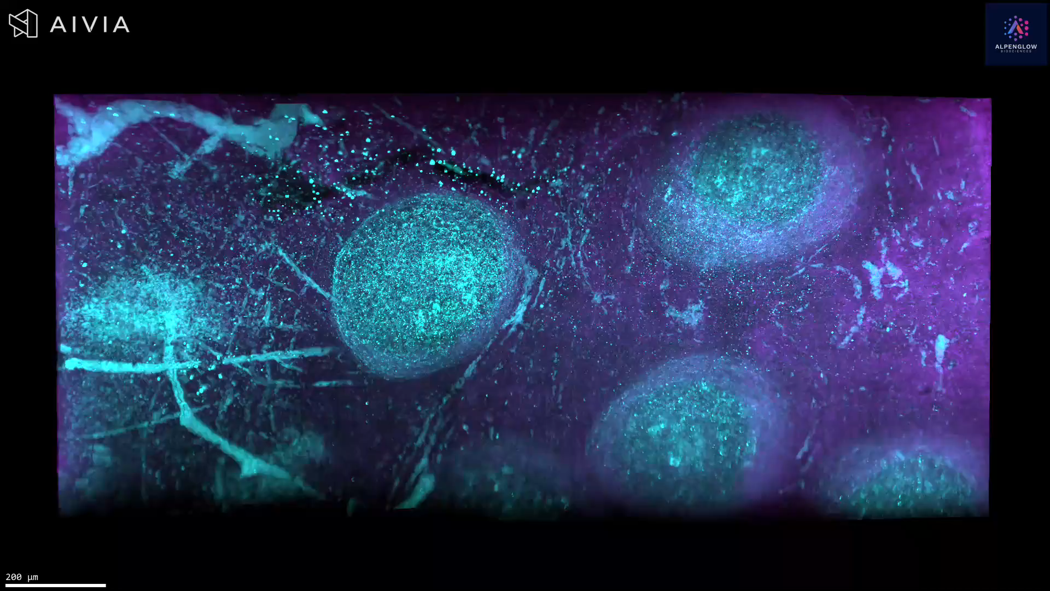

3D Imaging of Human Tonsil Tissue Highlighting Mast Cells with Tryptase Staining

3D view of human tonsil tissue stained with YO-PRO-1 and Tryptase, revealing mast cell distribution and spatial organization in unprecedented detail.